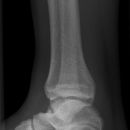

Sprunggelenk a.p.

Freier Einblick in den kompletten Gelenkspalt? (Aufnahme in 15-20° Innenrotation, beide Malleolen in gleicher Tischplattenentfernung!) -> Kontur der Incisura fibularis tibiae und laterale Talusrollenkontur in einer Fluchtlinie?

• Weite (lateral 4-5mm, medial 3-4mm) und Kongruenz des Gelenkspalts

• Syndesmosenspalt < 5mm

• Fluchtlinie von Incisura fibularis und lateraler Talusrollenkontur -> Versetzung weist auf (osteo-)ligamentäre Verletzung hin!

• tibiofibulare Gelenkkontur

• Weichteilschwellung (v.a. ventral des Gelenkspaltes in der seitlichen Aufnahme und um den lateralen Malleolus in der ap.-Projektion)